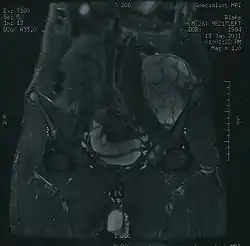

MRI of a left-pelvis chondrosarcoma in a 26-year-old male

Imaging studies – including radiographs ("x-rays"), computerized tomography (CT), and magnetic resonance imaging (MRI) – are often used to make a presumptive diagnosis of chondrosarcoma.[9] However, a definitive diagnosis depends on the identification of malignant cancer cells producing cartilage in a biopsy specimen that has been examined by a pathologist. In a few cases, usually of highly anaplastic tumors, immunohistochemistry (IHC) is required.

There are no blood tests currently available to enable an oncologist to render a diagnosis of chondrosarcoma. The most characteristic imaging findings are usually obtained with CT.[10]